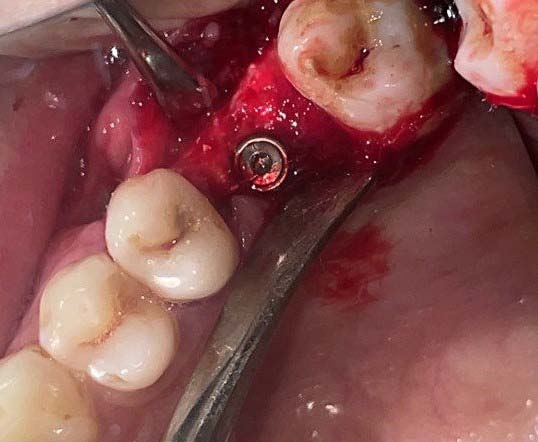

Une perforation de la branche montante est réalisée, sous irrigation, grâce à une fraise boule montée sur pièce à main chirurgicale, afin de faire passer le fil d'ostéosynthèse de part et d'autre, en protégeant le nerf lingual.

Un fil d'ostéosynthèse (de 4/10 ème de mm de diamètre) est ensuite inséré dans la perforation. Les deux brins seront toronnés et repliés au niveau de l'appareil d'orthodontie pendant le geste chirurgical afin de ne pas gêner le patient. La mise en traction par l'orthodontiste peut avoir lieu rapidement après la mise en place du système.